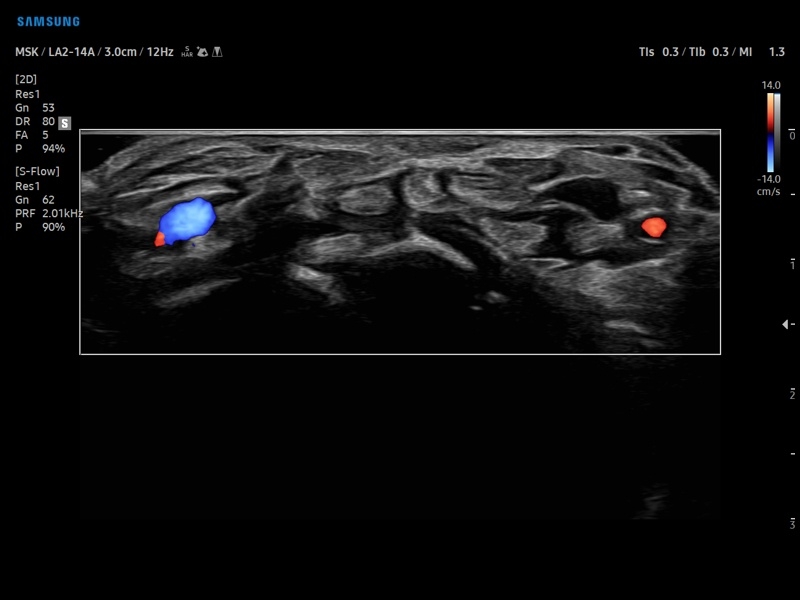

Ультразвуковой сканер V8-RUS является экспертным классом (премиальный уровень) и производится компанией Samsung Medison. Сканер V8 обеспечивает превосходное качество изображения благодаря использованию технологии Crystal Architecture™, которая включает в себя передовое аппаратное обеспечение, монокристальную технологию изготовления датчиков и сложную программную обработку ультразвуковых лучей.

Samsung Medison V8 представляет собой современную ультразвуковую систему, в которой воплощен многолетний опыт компании Samsung в создании эргономичного и интеллектуального диагностического оборудования. Система оснащена передовыми инструментами автоматизации, которые значительно упрощают рабочий процесс и повышают эффективность исследований.

• Диагностика костно-мышечной системы

• Модуль MV-Flow – программа (режим), позволяющая визуализировать кровоток в микроциркуляторном русле с высоким разрешением без использования контраста.

• Программа SEE Stream – режим недопплеровской визуализации кровотока в реальном масштабе времени.

• Модуль MV-Flow - программа (режим), позволяющая визуализировать кровоток в микроциркуляторном русле с высоким разрешением без использования контраста.